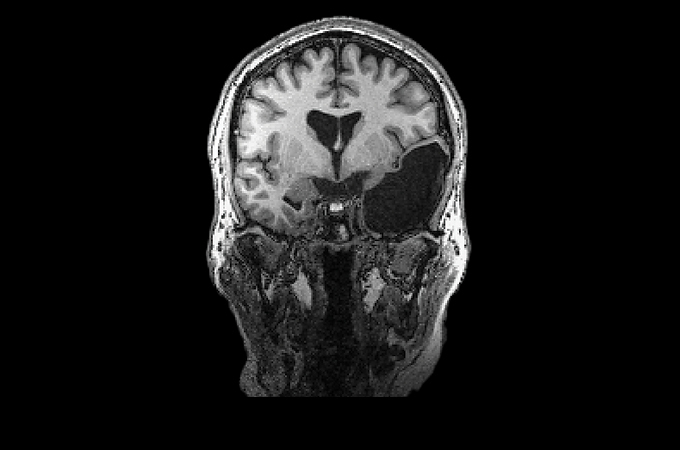

У Марты М., младшей сестры Элизы Г., также отсутствует большая часть височной доли, но на правой стороне мозга - почти зеркальное отражение поражения Элизы. Возможно, Марта перенесла инсульт еще в утробе матери. Позже скопление жидкости в мозге давило на нервы ее глаз, что мешало ей видеть. Как и у всех участников проекта "Интересный мозг", у Марты по языковым и когнитивным задачам средний балл или выше среднего.

Элайза больше не возвращалась к этим врачам, но летом она получила второе мнение от нейрохирурга своей сестры. Он оперировал Марту, когда ей было 17 лет, после того как она заметила проблемы со зрением. Большая часть правой височной доли отсутствовала, возможно, в результате внутриутробного инсульта. Жидкость, скопившаяся в мозге, давила на нервы глаза, мешая зрению. "Они откачали жидкость, и я пошла своей дорогой", - говорит Марта. С тех пор ей больше не делали дренирование этой области.

Элайза и ее сестра Марта М., которые не называют своих полных имен, чтобы сохранить анонимность, выглядят и ведут себя совершенно обычно. Но у каждой из них отсутствует большая часть височной доли, причем в разных полушариях. У Элизы также отсутствует часть ствола мозга. Эти женщины - две из тех, кто знает, сколько людей прожили свою жизнь без структур мозга, которые обычно считаются важнейшими.